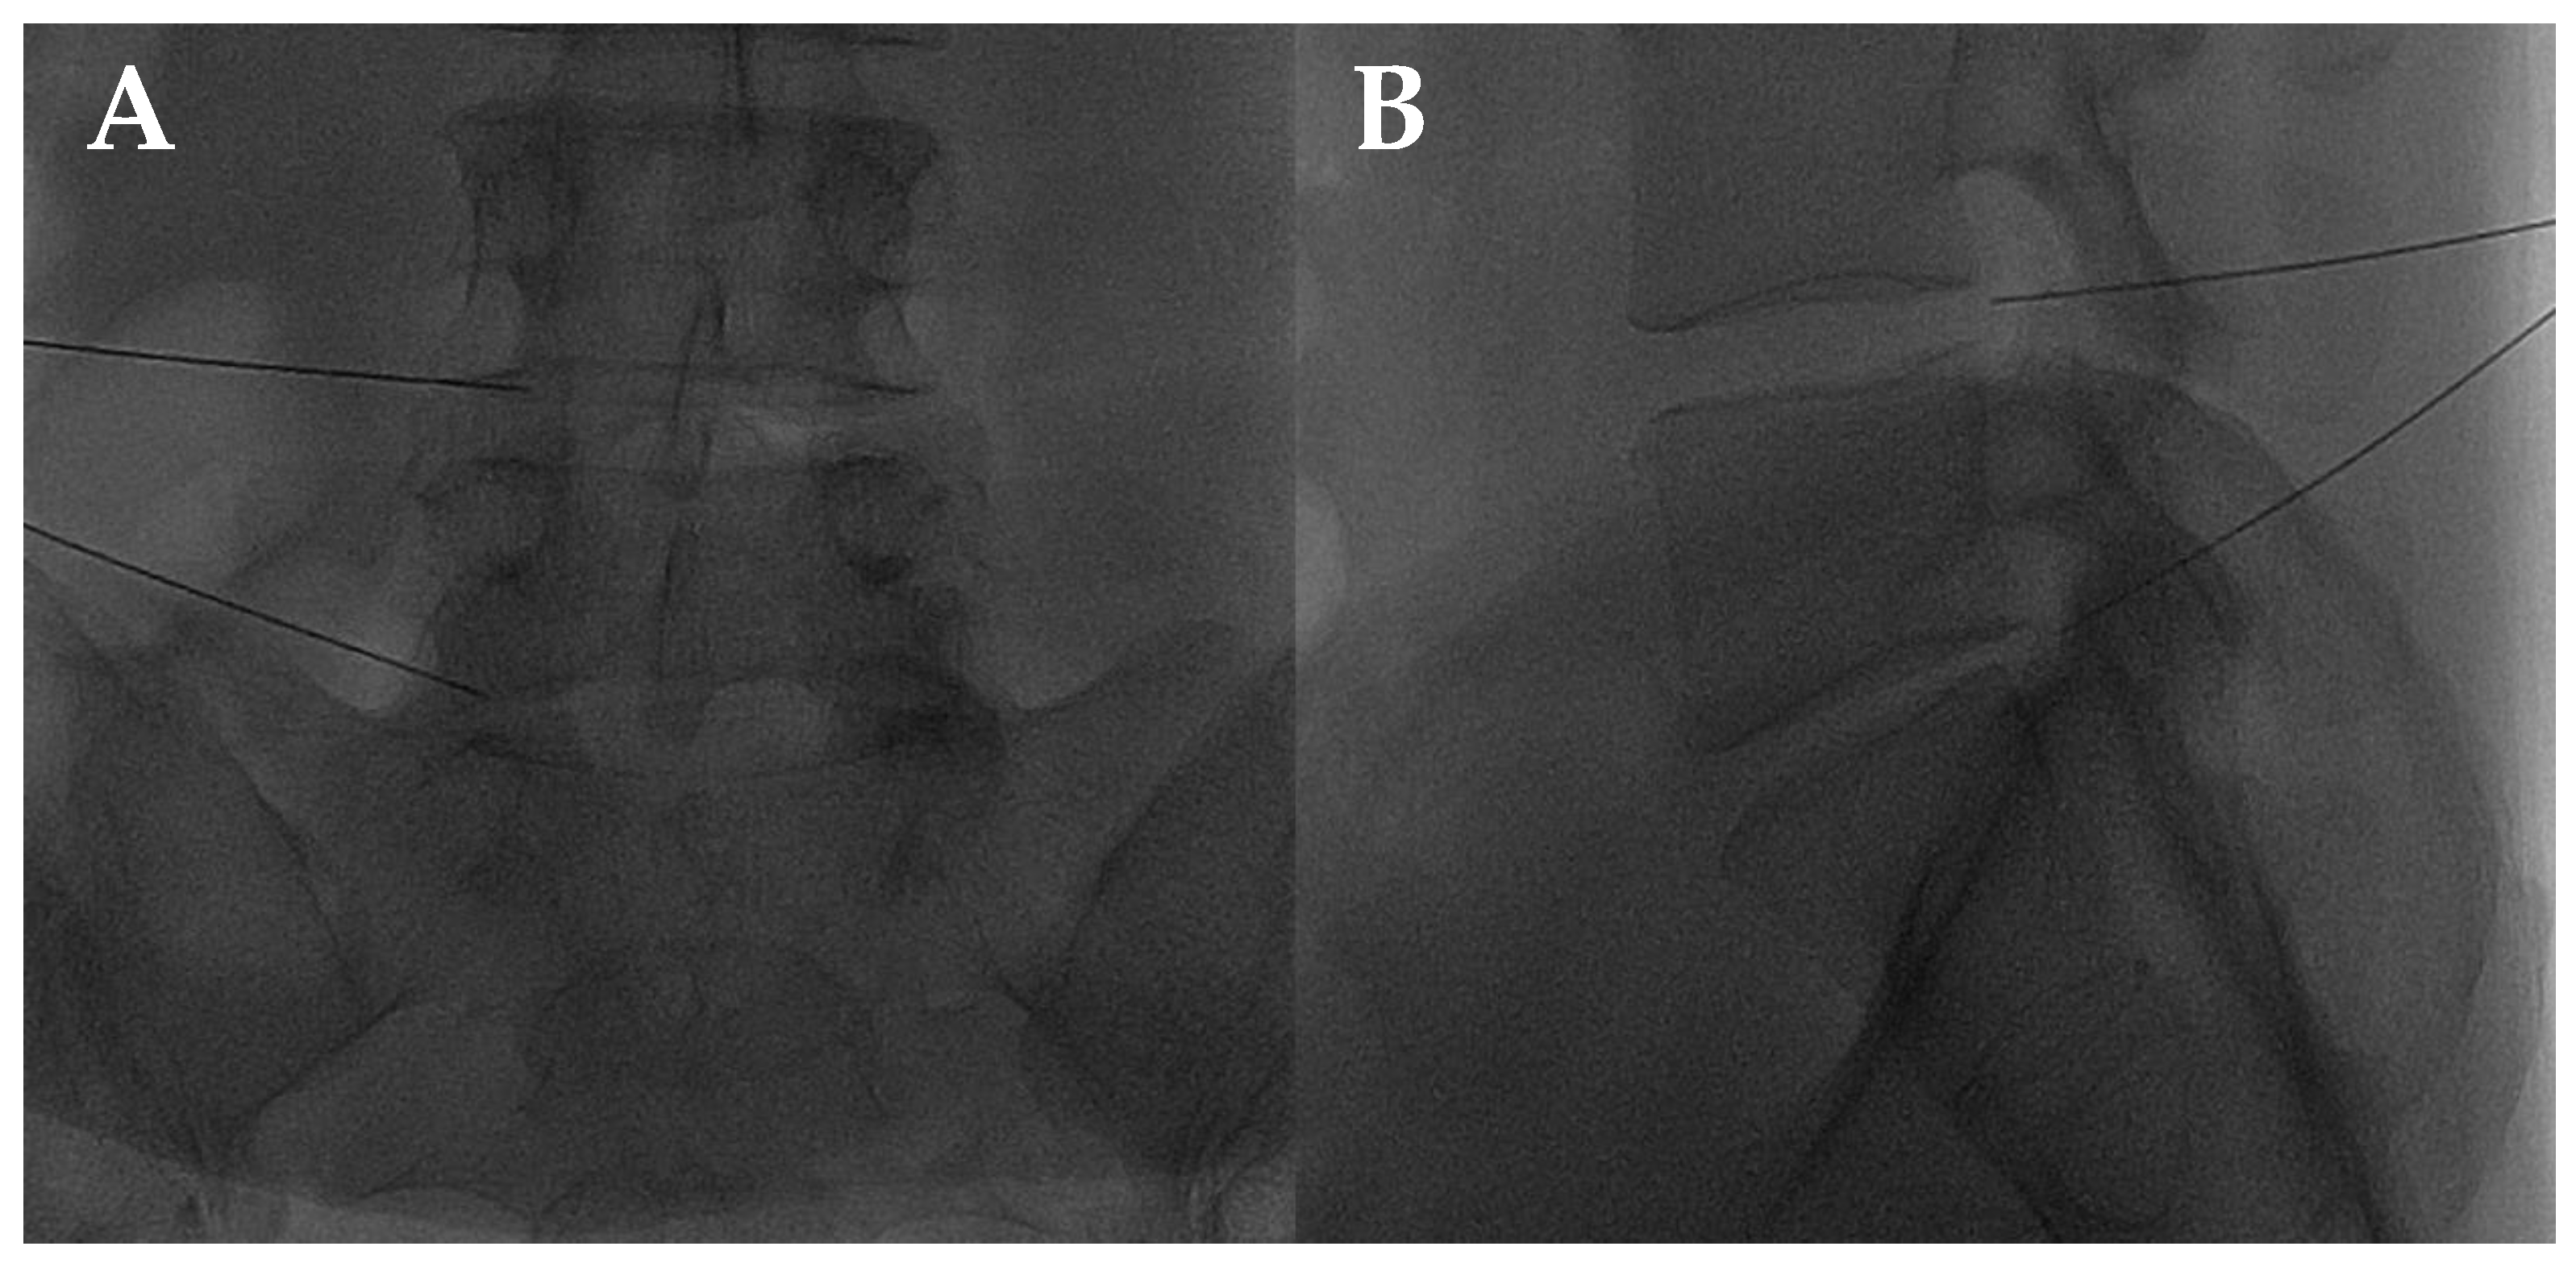

- Giurazza, F.; Guarnieri, G.; Murphy, K.J.; Muto, M. Intradiscal O2O3: Rationale, Injection Technique, Short- and Long-term Outcomes for the Treatment of Low Back Pain Due to Disc Herniation. Can. Assoc. Radiol. J. 2017, 68, 171–177. [Google Scholar] [CrossRef] [PubMed]

- Muto, M.; Ambrosanio, G.; Guarnieri, G.; Capobianco, E.; Piccolo, G.; Annunziata, G.; Rotondo, A. Low Back Pain and Sciatica: Treatment with Intradiscal-Intraforaminal O(2)-O(3) Injection. Our Experience. Radiol. Med. 2008, 113, 695–706. [Google Scholar] [CrossRef]

- Bonetti, M.; Fontana, A.; Cotticelli, B.; Volta, G.D.; Guindani, M.; Leonardi, M. Intraforaminal O(2)-O(3) versus periradicular steroidal infiltrations in lower back pain: Randomized controlled study. Am. J. Neuroradiol. 2005, 26, 996–1000. [Google Scholar]

- Andreula, C.F.; Simonetti, L.; De Santis, F.; Agati, R.; Ricci, R.; Leonardi, M. Minimally invasive oxygen-ozone therapy for lumbar disk herniation. Am. J. Neuroradiol. 2003, 24, 996–1000. [Google Scholar] [PubMed]

- Zhang, Y.; Ma, Y.; Jiang, J.; Ding, T.; Wang, J. Treatment of the lumbar disc herniation with intradiscal and intraforaminal injection of oxygen-ozone. J. Back. Musculoskelet. Rehabil. 2013, 26, 317–322. [Google Scholar] [CrossRef]

- Muto, M.; Andreula, C.; Leonardi, M. Treatment of herniated lumbar disc by intradiscal and intraforaminal oxygen-ozone (O2-O3) injection. J. Neuroradiol. 2004, 31, 183–189. [Google Scholar] [CrossRef] [PubMed]